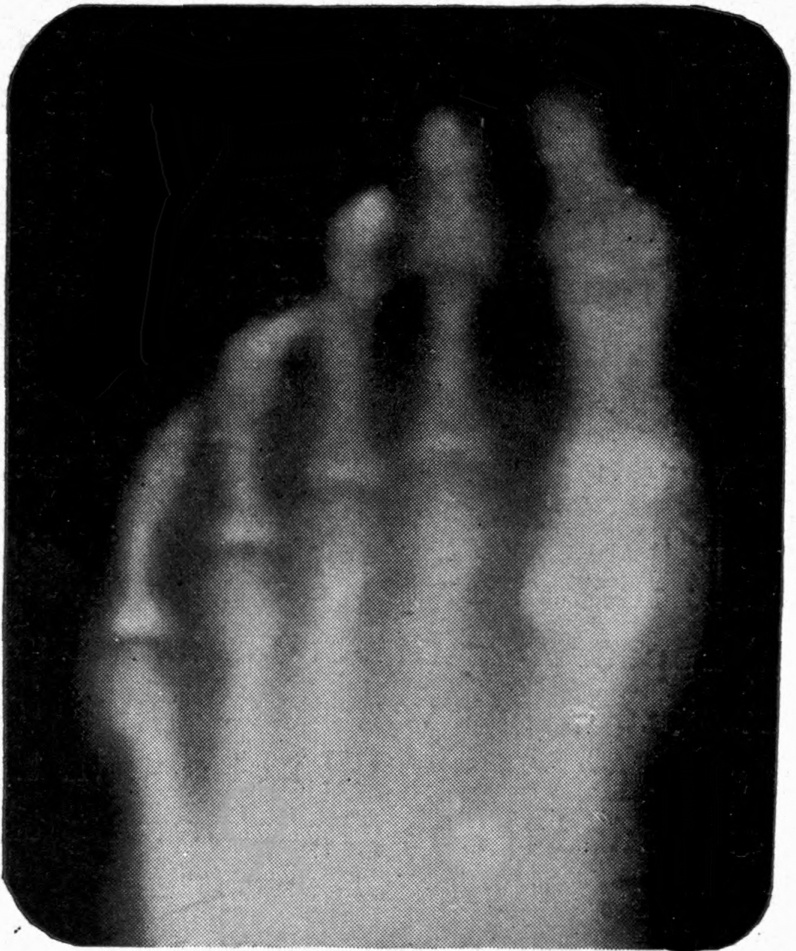

Fig. 1.—Head.

Fig. 2.—Broken Arm, Overlapping.

(Due to defective setting.)

Fig. 3.—Ribs.

Fig. 4.—Knee, Knickerbocker Buttons, Bullet in Femur.

FROM SCIAGRAPHS BY PROF. DAYTON C. MILLER. § 204.